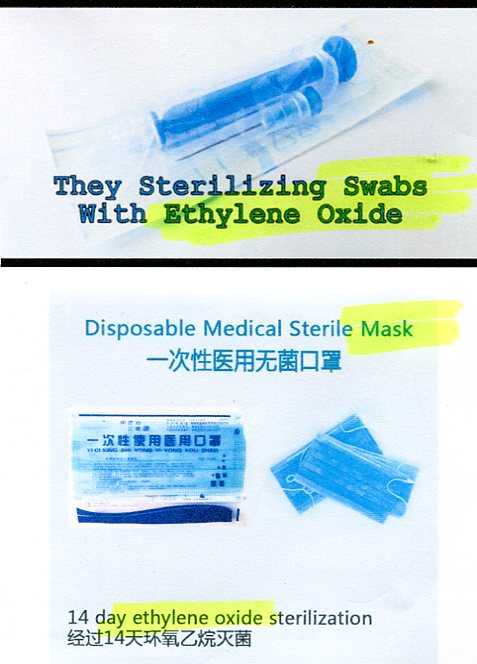

Serious issues with chemicals in at-home COVID tests

watch Carcinogenic EO in swab up nose & mask on face

watch How to use deadly NaN3 self-test COVID kit

News/YouTube, Jan 10, 2022